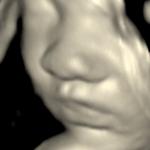

Peek-A-Boo Package - $99

- 10 Minute 3D/4D Session

- CD with 25+ Images

- Gender Reveal upon request

- Hear your baby's heartbeat